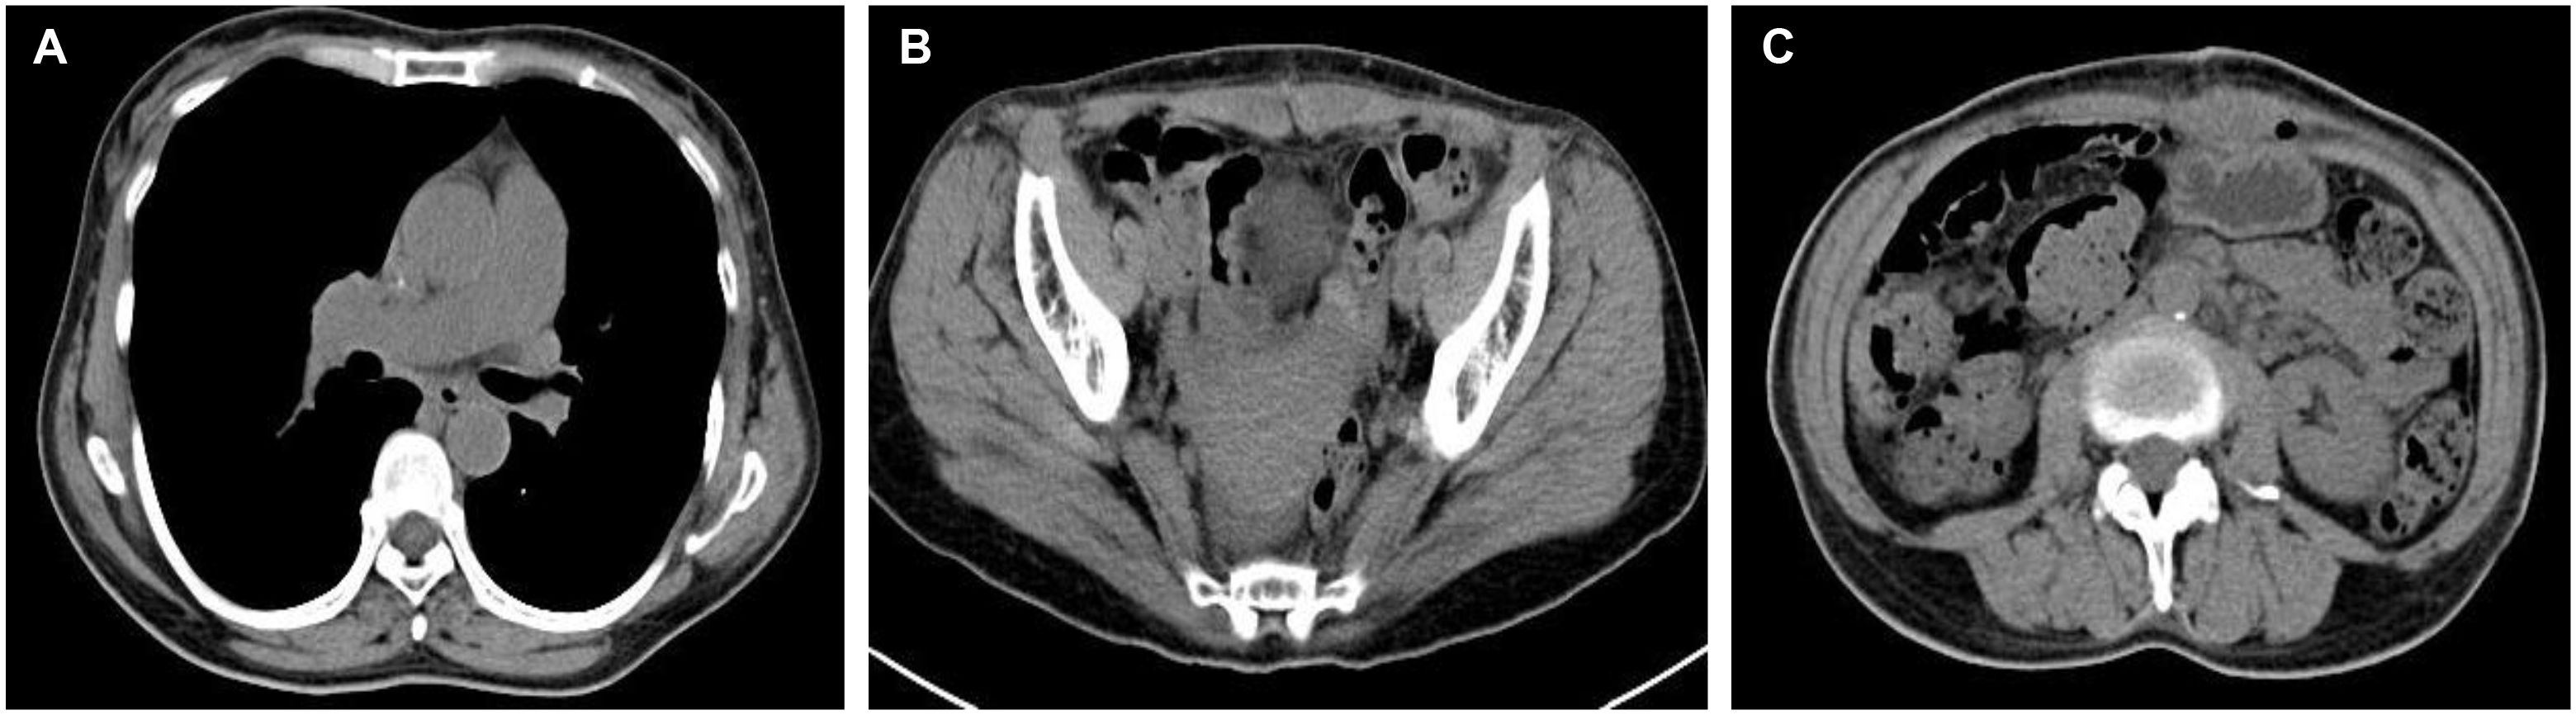

On April 30, 2024, the patient underwent surgical treatment, including skin incision, electrosurgical incision of subcutaneous fascia, and blunt dissection of the rectus abdominis muscle. The peritoneum was opened, revealing approximately 200 ml of clear, pale yellow ascitic fluid. The uterus appeared normal, and the right ovary and fallopian tube were unremarkable. The left ovary was significantly enlarged, presenting a mass measuring 25 × 20 × 20 cm, with an intact capsule and predominantly solid characteristics. The left fallopian tube was thickened and adhered to the mass, prompting a left adnexectomy (Figures 2A). Hemostasis was achieved by clamping the pelvic funnel ligament, isthmus of the fallopian tube, and ovarian ligament, followed by cutting and suturing. The left adnexa was sent for frozen section examination, which suggested benign characteristics. A thorough exploration of the abdominal cavity revealed no other abnormalities. Post-operative pathology demonstrated: immunohistochemistry results of CD10 (+), CD117 (-), CEA (+), Desmin (-), DOG-1 (-), EGFR (+), ER (-), Ki-67 (approximately 1%+), P53 (-), PAX-8 (-), PR (+), S-100 (-), SMA (-), Vim (+), VEGF (-), and inhibin-a (+). The pathological results confirmed it as a follicular membrane tumor of the left ovary, with no sign of malignant tumor (Figures 2B–D). The final diagnosis was Meigs syndrome. The patient was discharged on May 11, 2024, with good post-operative recovery. Nine days post-surgery, the patient’s CA125 level decreased to 164.6 U/ml. Post 1 week CT of the thorax and abdomen showed complete resolution of pleural effusion and ascites (Figures 3A, B), abdominal CT showed no sign of tumor recurrence (Figures 3C). Two weeks post-surgery, the CA125 level returned to normal.

Figure 3. Post 1 week CT of the thorax and abdomen. (A) CT chest showed complete resolution of right-sided pleural effusion; (B) Abdominal CT showed the disappearance of ascites; (C) Abdominal CT showed no sign of tumor recurrence.